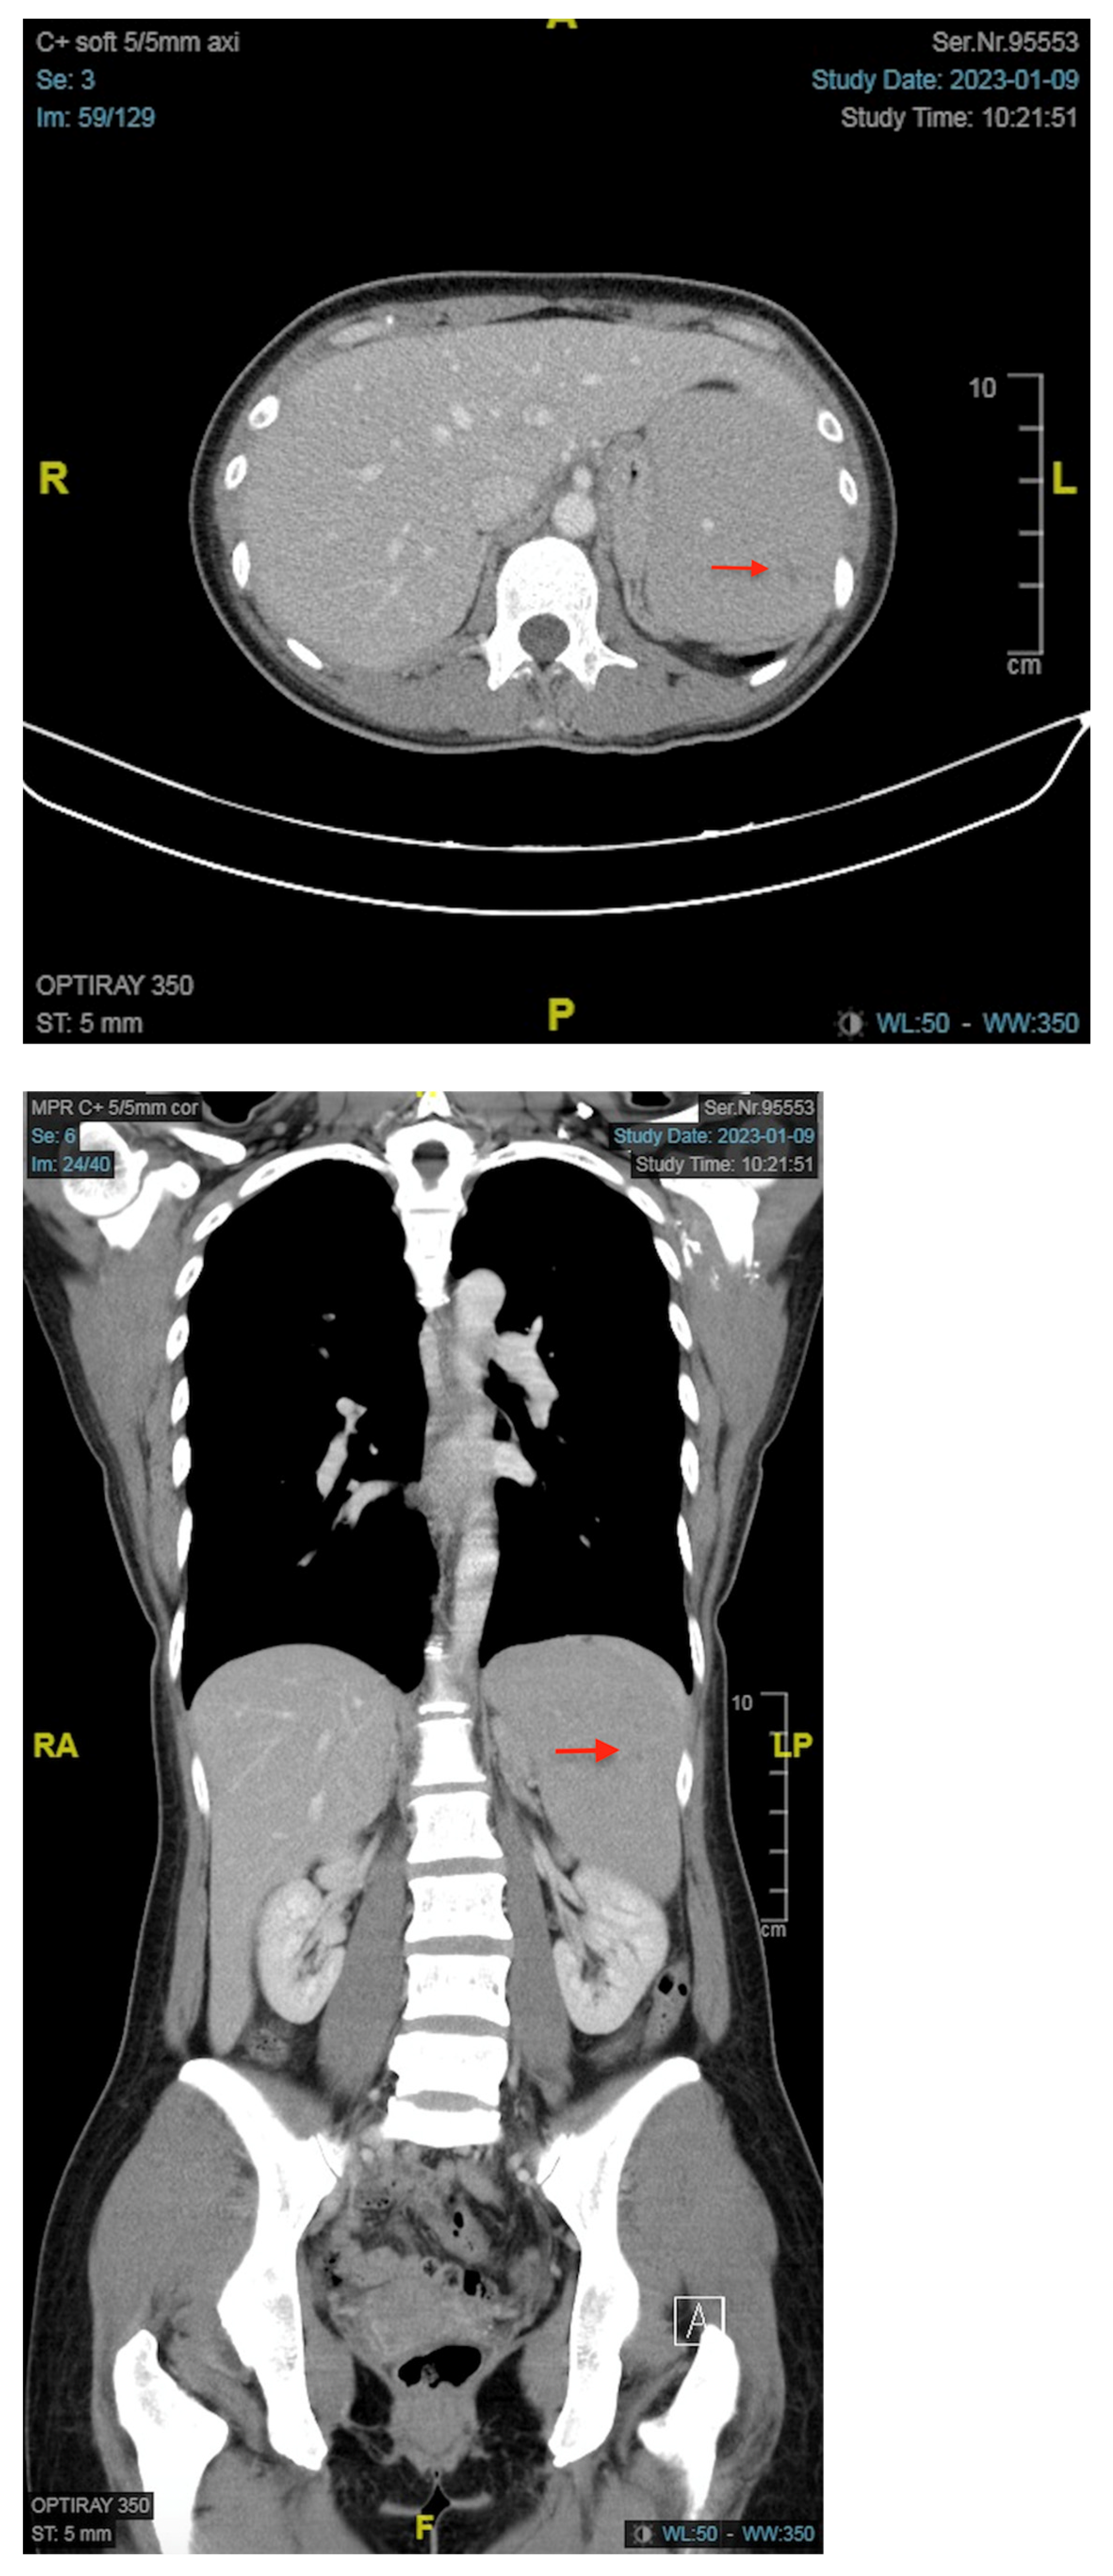

2. Case Report